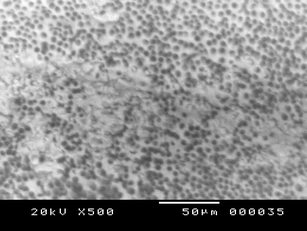

Cleaning and disinfection of the root canal system are some of the most important goals in endodontic therapy. The aim of this preliminary study is to assess the effectiveness of Er:YAG laser fiber in removing the smear layer produced during root canal walls instrumentation. Forty-eight single-rooted teeth were prepared with manual and rotary Ni-Ti instruments, in addition to 2.5 % NaOCl irrigation. Samples were randomly subdivided into groups and treated with: three irradiations of 5 s each, with 300-μm Er:YAG endodontic fiber, 1 W and 2.5 % NaOCl solution (A Group); two laser irradiations with 17 % EDTA solution and 2.5 % NaOCl solution (B Group); laser irradiation plus 17 % EDTA solution and 2.5 % NaOCl (C Group); only in the final wash of 17 % EDTA (control group D). During laser treatment, temperature variations were analyzed by using thermocouple and thermal camera devices in order to test both deep and superficial temperatures. Each sample was finally observed by scanning electron microscope (SEM) at the coronal, medium, and apical thirds at ×500 magnification and blindly scored depending on the amount of smear layer. Statistical analysis of the results was conducted using the Kruskal–Wallis and Mann–Whitney test to determine the eventual significant differences between the quantity of smear layer in each group and between the groups at coronal, medium, and apical third: a p value <0.05 was considered significant. The thermal analysis realized by thermocouple with the used parameters demonstrated that laser endodontic fiber produces an average deep temperature increase of 3.5 ± 0.4 °C; analysis performed with a thermal camera showed an average superficial temperature increase of 1.3 ± 0.2 °C produced by laser endodontic fiber use. Deep and superficial temperatures fall immediately after irradiation possibly without causing structural damage or anatomical alteration inside the root canal and neither on periodontal tissues. SEM analysis showed that specimens of group B had the highest level of cleaning in every third, with a significant difference with groups D and A; group C samples showed a good percentage of cleaned tubules in apical and middle thirds, while group D teeth showed open dentinal tubules in coronal third, with a statistical difference with group A samples which were the worst cleaned. The Er:YAG fiber double irradiation with EDTA 17 % and NaOCl 2.5 % has been demonstrated to be effective in removing smear layer, even in the apical third which is described as the hardest area to clean during endodontic treatment.

Fig. 1

Fig. 2

Fig. 3

Fig. 4

Fig. 5

Fig. 6